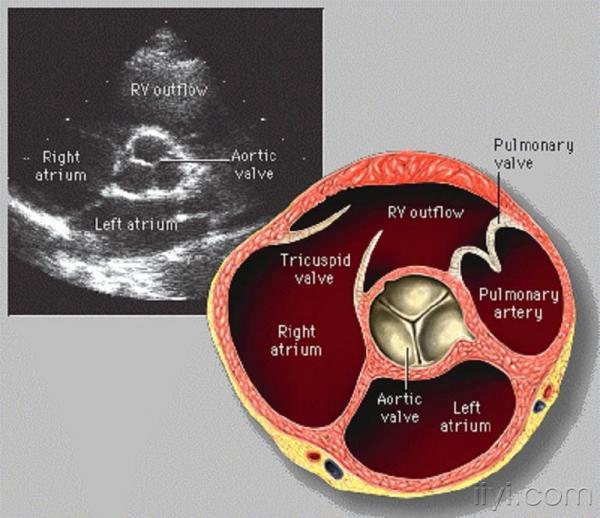

超声心动图-主动脉瓣

也许我们对心脏瓣膜的解剖可能已经烂熟于心,然而,在超声心动图中,各